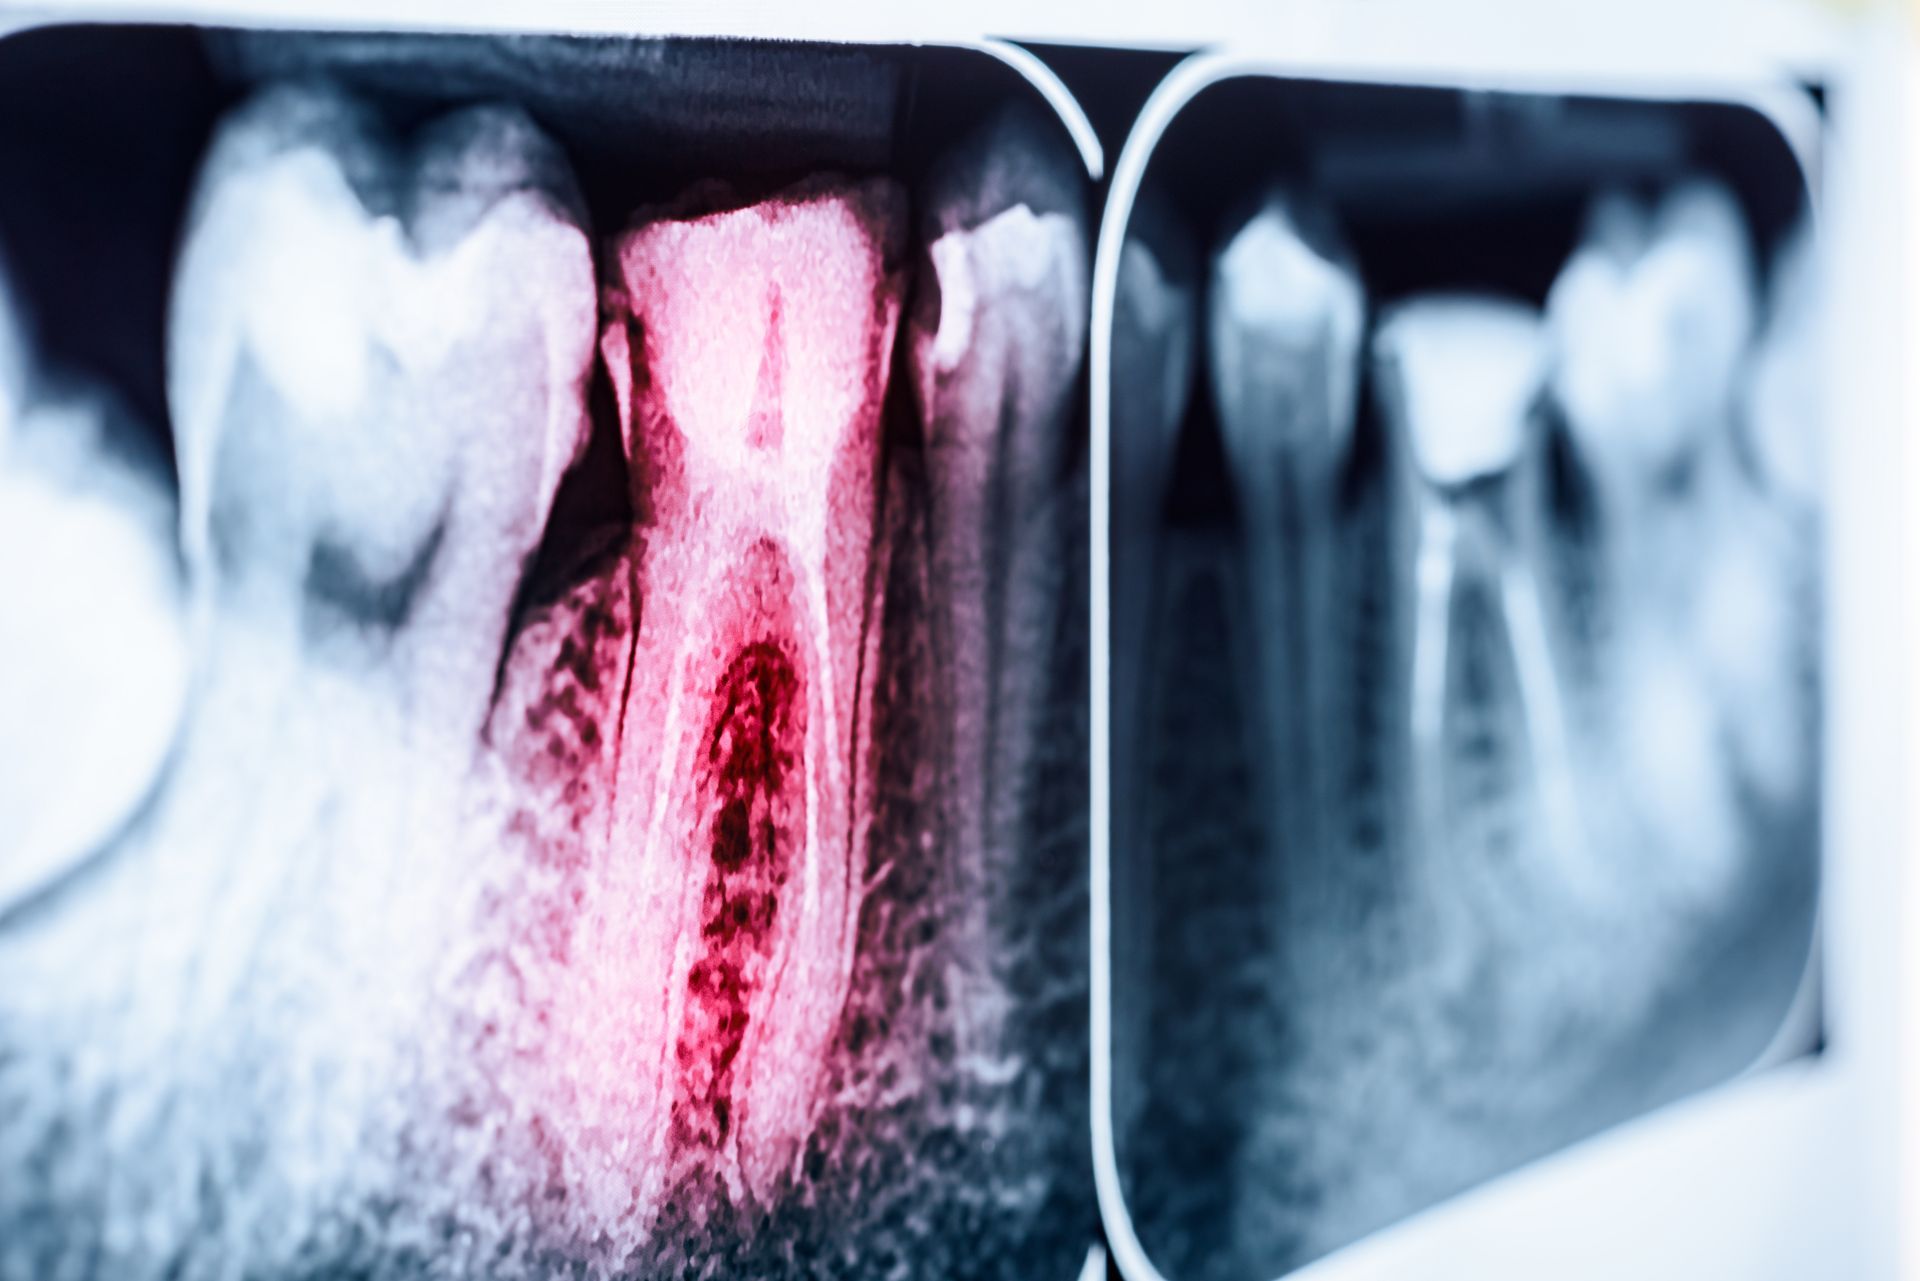

Diagnosis begins with a comprehensive dental exam, including measurement of gum pocket depths and evaluation of bone levels through diagnostic imaging. The severity of gum disease determines the recommended treatment approach.

- Monitoring gum pocket depths and bone levels